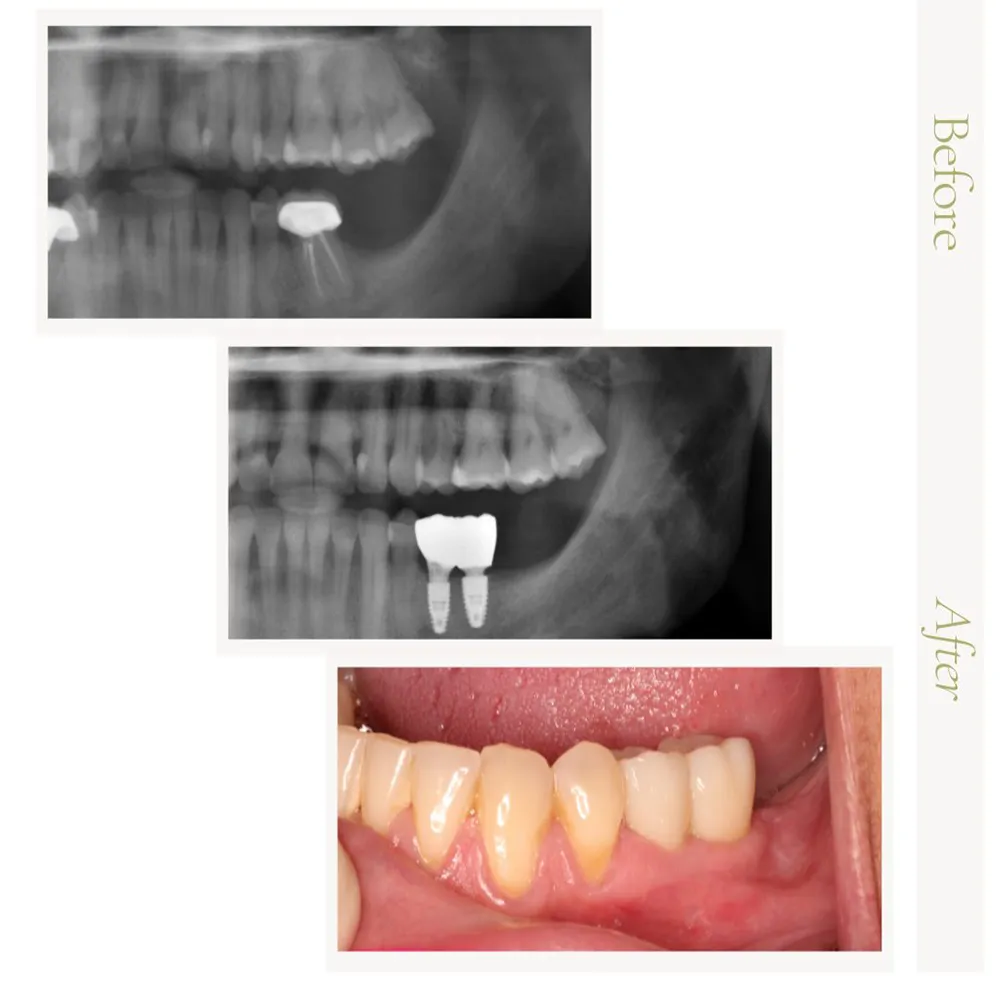

In the gallery below, you’ll find a selection of real patient results that reflect the quality and precision of our surgical care. If you’re inspired by the transformations you see and are considering a visit, we invite you to contact our office at 623-931-9197. A member of our team will be glad to assist you in scheduling your consultation.